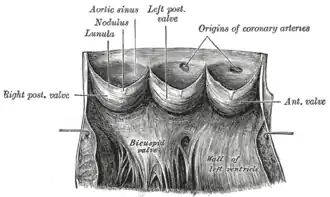

| Aorta laid open to show the semilunar valves. (Aortic sinus, also known as "sinus of Valsalva", is labeled at upper left.) | |

Aneurysm of the aortic sinus, also known as the sinus of Valsalva, is a rare abnormality of the aorta, the largest artery in the body. The aorta normally has three small pouches that sit directly above the aortic valve (the sinuses of Valsalva), and an aneurysm of one of these sinuses is a thin-walled swelling. Aneurysms may affect the right (65–85%), non-coronary (10–30%), or rarely the left (< 5%) coronary sinus.[1] These aneurysms may not cause any symptoms but if large can cause shortness of breath, palpitations or blackouts. Aortic sinus aneurysms can burst or rupture into adjacent cardiac chambers, which can lead to heart failure if untreated.